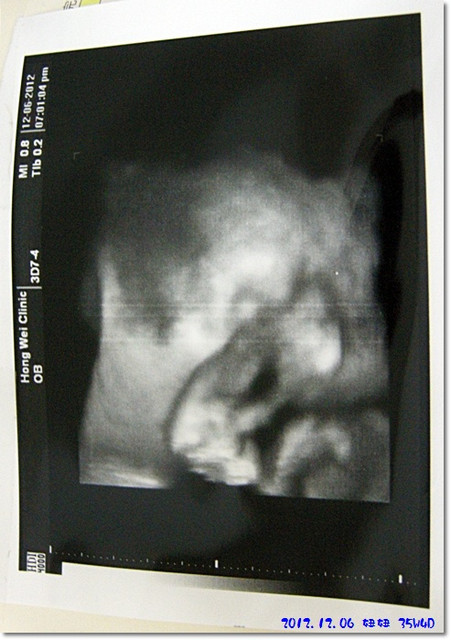

下面這張就是妞妞的3D圖像...

妞妞的手一直擋在她的臉面前,都不露出真面貌內![]()

把圖片轉個方向看應該會比較清楚一點也比較可以意會吧...

我個人是看不太出來啦

,虧陶醫師一直在跟我解釋圖像的樣子

我還是有看沒有懂呀![]()